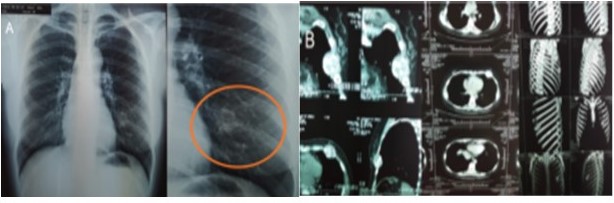

Entre los estudios de imágenes que se realiza, muestra una de RX tórax simple AP-L de 2019, donde se observa derrame pleural izquierdo con desplazamiento del cardiomediastino a la derecha (Figura 1B). Una RX de tórax PA de 2012 donde se evidencia cambios en la densidad ósea del 5o arco costal anterior izquierdo con pérdida de la cortical y TAC de tórax con contraste del mismo año en la cual se identifica un tumor de 4 cm x 5 cm en el 5o arco costal, de bordes definidos, de crecimiento expansivo con línea fina de cortical residual de la costilla sin signos de extensión a tejidos blandos, tórax o mama (Figura 2). En abril de 2019 realiza tomografía de tórax (Figura 3) con contraste y reconstrucción en 3D, donde se observa una lesión de 30 cm x 20 cm, que compromete 4o 5o y 6o arco costal anterior, expansiva, lítica, bordes mal definidos con destrucción de la cortical, desplazando pulmón izquierdo y mediastino sin infiltrarlos, compromete la totalidad de la mama izquierda, en relación íntima con el pericardio desplazándolo a línea media y derrame pleural izquierdo masivo.